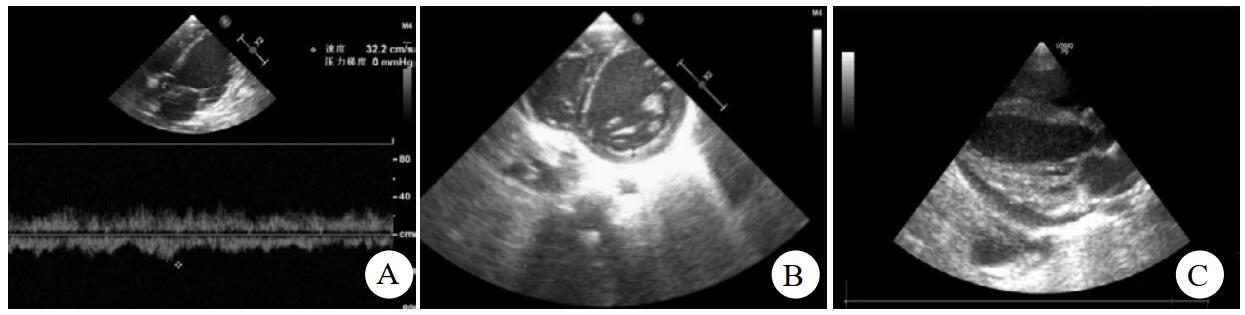

A:病例2左心增大,主动脉瓣流速32.2 cm/s;B:病例2左心增大,室间隔右移;C:病例3左心增大,心包积液 图 1 病例2、病例3心脏超声影像

病例2,女,2岁8月,10.2 kg,诊断:⑴暴发性心肌炎;⑵心功能衰竭。入院时VIS评分40分,血压70/55 mmHg(1 mmHg=0.133 kPa),pH 7.298,BE -5.4,乳酸(lactic acid, LAC)2.7 mmol/L。心超提示:左室增大(3.4 cm),左心收缩功能减低(EF 29%)。入科后立刻镇静插管,半小时内建立V-A ECMO。颈总动脉置入12 Fr美敦力插管,颈内静脉置入14 Fr美敦力插管。膜肺型号米道斯2400,泵速2 815~3 188 r/min,流量0.47~0.92 L/min,膜前静脉血氧饱和度56%~90%。ECMO上机后20 h。床边心超提示:左室增大(4.1 cm),EF 20%,左室内血液涡流,主动脉瓣开合欠佳。立即于左心耳置入14 Fr引流管。左心减压后,患儿病情逐渐平稳,ECMO运行第5天,患儿左心功能逐渐恢复,撤除左心减压管。撤除左心减压管过程中,ECMO系统肝素维持在28~34 μg/(kg·h),活性凝血时间(activated coagulation time, ACT)维持在142~190 s之间,术后伤口敷料干洁,未见渗血。撤除减压管后约12 h,患儿血气结果提示红细胞压积(hematocrit, HCT)进行性下降,考虑存在内出血可能,立即行床边超声检查,提示左侧胸腔积液(6.0 cm)。立即停用肝素,并输注纤维蛋白原,红细胞1 U等对症处理后,出血症状好转。36 h后开胸清创,吸出陈旧性血液约600 mL。ECMO运行第8天,逐渐降低活性药条件,患儿各项生命支持稳定,成功撤除ECMO。患儿清醒后,无意识障碍,左上肢肌力3级,左下肢肌力2级,完善头颅磁共振检查示:右侧基底节及侧脑室旁低密度灶。对症治疗后,患儿康复医院进一步就诊。

病例3,女,5岁11月,20.0 kg,诊断:⑴暴发性心肌炎;⑵心律失常,室性心动过速。上机时VIS评分50分,心率150次/min,室性心律为主,血压难以测出。pH 7.25,LAC 6.7 mmol/L,PO2 20 mmHg。床边心超提示全心增大,左室壁活动整体减低(EF 28%)。心电图示室性心律。半小时内建立V-A ECMO。颈总动脉置入16 Fr美敦力插管,颈内静脉置入17 Fr美敦力插管。膜肺型号米道斯2400,泵速3 325~3 555 r/min,流量0.89~1.37 L/min,膜前静脉血氧饱和度55%~75%。ECMO系统肝素从8 μg/(kg·h)逐步调至24 μg/(kg·h),ACT维持在160~180 s。ECMO上机后24 h,动态监测床边心超提示:左室进行性增大(3.8 cm至4.4 cm),EF维持30%左右,主动脉瓣开合欠佳。评估后于左心房置入17 Fr引流管。此时停用ECMO系统肝素24 h,ACT维持在150~170 s之间。确定患儿伤口无渗血,胸引液无明显增多,血气中HCT稳定后,再次5 μg/(kg·h)起步使用ECMO肝素,逐步加量,保持ACT在160~180 s之间。左心减压后,患儿心律逐渐恢复至窦性,心音渐强,VIS评分逐步下调至28分。ECMO支持80 h,左心减压56 h后,患儿出现双侧瞳孔不等大,对光反射迟钝。紧急头颅CT示:右侧顶枕叶可见不规则片状高密度影及低密度灶,血肿(部分已吸收)破入脑室,中线明显左偏。家属放弃治疗,撤除ECMO后患儿死亡。